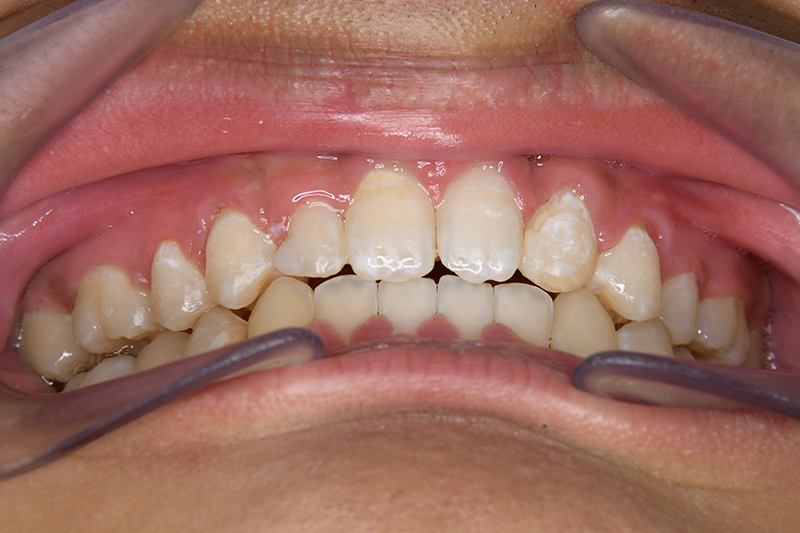

初診時

FP・IOP

主訴 すきっ歯 診断名 上顎右側犬歯先天欠如を伴うアングルⅡ級空隙歯列症例

初診時年齢 15歳5ヵ月 性別 動的治療期間 21ヵ月

口腔内所見 over jet 8.0mm、over bite 8.0mmで下顎歯列はスピー湾曲が強く、過蓋咬合、上突歯列、叢生歯列を呈しており、臼歯関係はⅡ級、左側7は鋏状咬合となっていた 。上顎両側2は矮小歯で上顎右側Cは晩期残存をしていた。また上顎歯列は空隙歯列を呈していた。